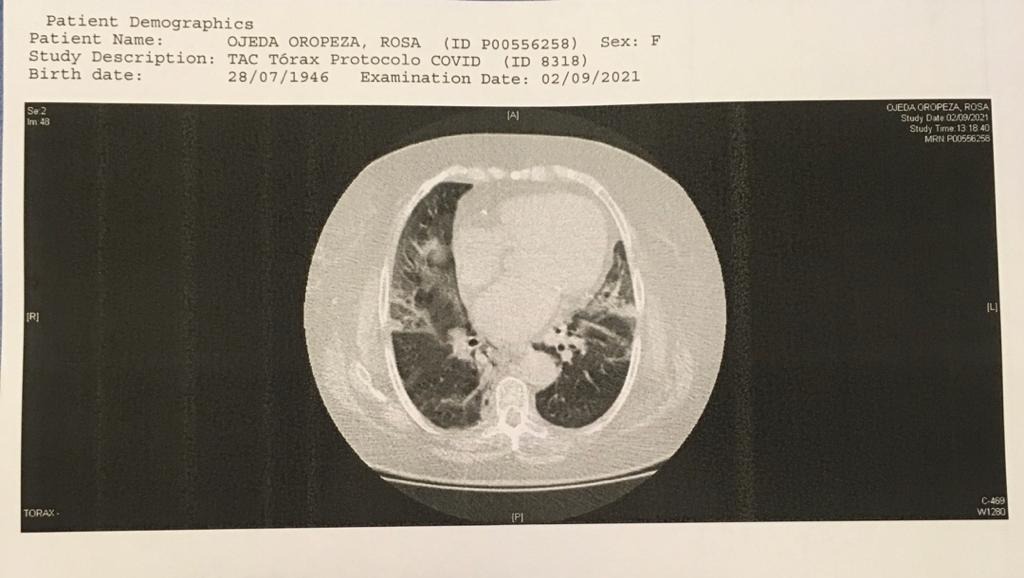

Hola, soy Sandu Arias, hija de Rosita Ojeda, en estos momentos ella atraviesa por una delicada situación de salud, debido a que contrajo el virus del COVID 19. Presentando síntomas desde el pasado 28 de agosto, complicándose poco a poco hasta tener que internarla en la Policlínica Metropolitana el pasado jueves 2 de septiembre, ingresándola en cuidados intensivos, donde aun permanece. Actualmente no contamos con un seguro medico para ella, por lo que hemos agotado ya todos nuestros recursos económicos para continuar costeando los gastos clínicos, tomando en cuenta que mi mama deberá permanecer un tiempo mas recluida en la terapia para su recuperación, ya que la misma es un proceso lento.

Anexo soportes de informe medico, estudios complementarios y presupuesto de la clínica.